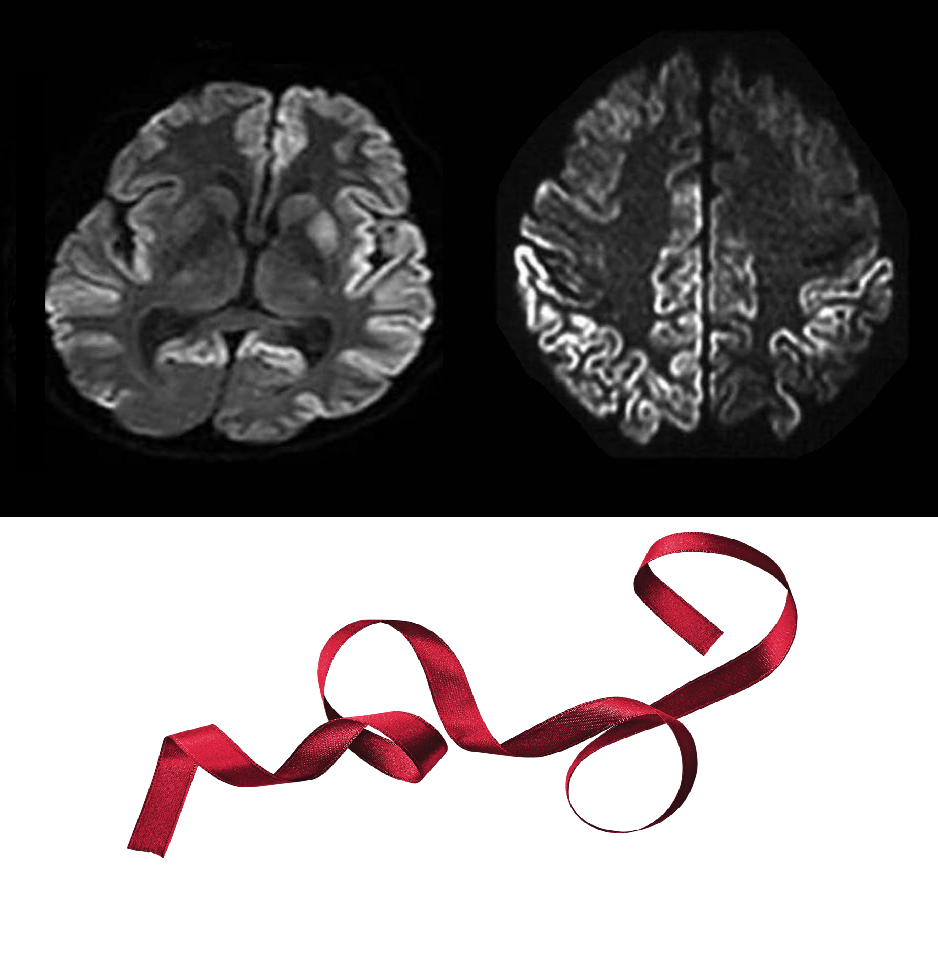

#ТелеМед_интересные_факты А вы знали, что при болезни Крейтцфельдта-Якоба на МРТ-снимках можно увидеть симптом "кортикальной ленты" (Сortical ribbon sign)? 🎋Диагностический признак получил свое название из-за криволинейного гиперинтенсивного сигнала, затрагивающего кору головного мозга на изображениях диффузионно-взвешенной визуализации с соответствующим низким сигналом на изображениях ADC. 📍Знак кортикальной ленты характерен для прионных заболеваний, а также может наблюдаться при тромбоокклюзионном инфаркте, эпилептическом статусе, инфекции, гипоксии, метаболических, электролитных и митохондриальных расстройствах.

А вы знали, что при болезни Крейтцфельдта-Якоба на МРТ-снимках можно увидеть симптом "кортикальной ленты" (Сortical ribbon sign)? 🎋Диагностический признак получил свое название из-за криволинейного гиперинтенсивного сигнала, затрагивающего кору головного мозга на изображениях диффузионно-взвешенной визуализации с соответствующим низким сигналом на изображениях ADC.

📍Знак кортикальной ленты характерен для прионных заболеваний, а также может наблюдаться при тромбоокклюзионном инфаркте, эпилептическом статусе, инфекции, гипоксии, метаболических, электролитных и митохондриальных расстройствах.